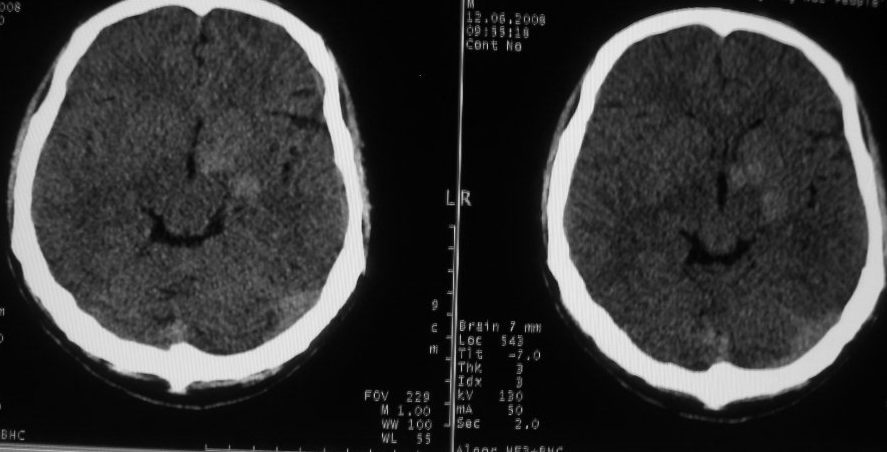

以下是引用守望可可西里在2008-6-13 1:25:00的发言:[br][br] 1.双侧大脑中动脉高密度踌型样接近于全程显示,部分大脑前动脉、基底动脉也呈高密度改变。[br] 2.右侧基底节多发类圆形ct值接近于出血的高密度,边缘模糊。双侧小脑幕及直窦、上矢状窦增宽、模糊。左侧横窦和乙状窦区密度增高、呈云雾状,内缘模糊。[br] 如果这样的表现发生在一个老年人脑部,我们首先会想到是高血压、动脉粥样硬化,就可以很容易得出结论。但这发生在一个20岁年青人的身上,且病程长达半年、临床症状不怎么重,这就比较蹊跷且应该引起高度重视了。[br] 我认为此病人应该是一个血液病患者--双侧大脑中动脉、部分大脑前动脉及基底动脉的高密度改变,只是一个假象:即相对于ct值偏低,只有35的脑灰质而言的相对高密度。而那么多出血改变,则是真正的病变表现。[br] 建议临床进一步进行其他相关的血液、骨髓检查,肝、脾也应该好好检查,应有明显的肿大。